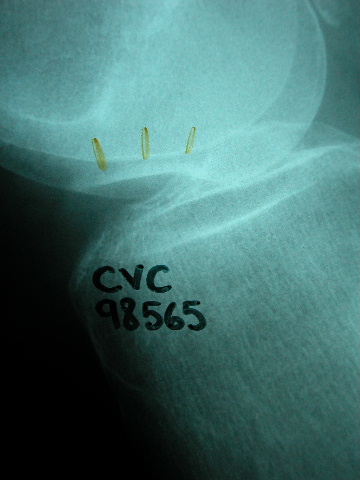

Densitometría en calcáneo